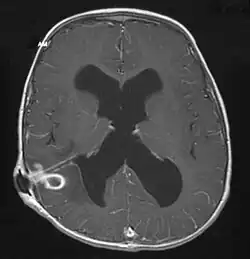

Brain abscess in a person with a CSF shunt. The abscess is the darker gray region in the lower left of the image (corresponding to the right parietal lobe). The lateral ventricles are visible in black in the center of the brain, adjacent to the abscess.[1] | |